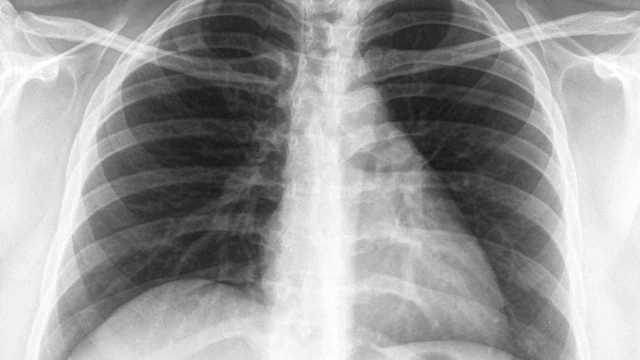

Chụp X quang và siêu âm là hai phương pháp chẩn đoán hình ảnh phổ biến, đóng vai trò quan trọng trong phát hiện và theo dõi nhiều bệnh lý khác nhau. Mỗi phương pháp đều có những ưu điểm, hạn chế và chỉ định riêng biệt. Việc so sánh chụp X quang và siêu âm sẽ giúp lựa chọn phương pháp phù hợp, nâng cao hiệu quả chẩn đoán và điều trị.

Chụp X-quang tầm soát u phổi là một trong những phương pháp chẩn đoán hình ảnh phổ biến được sử dụng để phát hiện sớm các bất thường trong phổi, đặc biệt là các khối u. Với khả năng nhanh chóng cung cấp hình ảnh về cấu trúc phổi, kỹ thuật này giúp bác sĩ đánh giá các tổn thương và đưa ra hướng điều trị kịp thời. Cùng Nhà thuốc Long Châu tìm hiểu chi tiết về chụp X-quang tầm soát u phổi trong bài viết dưới đây.